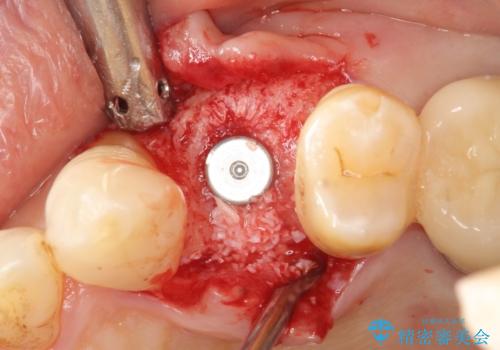

歯科治療や外科手術が苦手な患者様で、治療前はとても怖がっていましたが、インプラント手術後には「思ったよりも大変ではなかった」とおっしゃって下さいました。

インプラントの種類:スプライン ツイスト

被せ物の種類:メタルボンドクラウン

固定様式:スクリュー固定